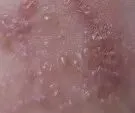

这种病毒初次感染人体时,会引发水痘,水痘痊愈后,病毒并未被彻底清除,而是潜伏在脊髓后根神经节或脑神经节内,进入“休眠状态”。当人体免疫力下降时,潜伏的病毒会被激活,沿着神经走向侵犯皮肤,引发带状疱疹。

带状疱疹最折磨人的,莫过于皮肤刺痛、灼痛,严重时甚至影响睡眠和进食,且疼痛可能在疱疹出现前就发生,容易被误诊。所以,当皮肤出现刺痛难忍的情况时,及时干预是关键,既能缓解不适,也能减少后遗症风险。

做好皮肤护理,保持患处清洁干燥,穿宽松、柔软的棉质衣物,避免摩擦、搔抓疱疹,防止破损感染。切勿自行涂抹偏方,以免刺激皮肤,加重病情。